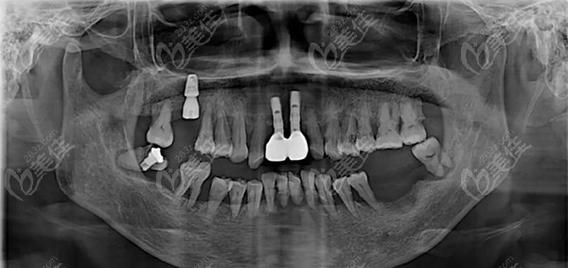

- 全景片(曲面断层片): 最常用,能一次性显示全口牙齿、牙槽骨、颌骨、上颌窦、下颌神经管等的大致情况,但它是二维影像,存在重叠和放大失真,对骨量评估精度有限。

- 锥形束CT(CBCT): 这是种植牙术前评估的“金标准”! 它能生成三维立体影像,提供牙槽骨高度、宽度、密度的精确数据,清晰显示神经管、上颌窦等关键结构的立体位置和形态,对于复杂病例(骨量不足、后牙区种植、即刻种植等),CBCT是必不可少的。